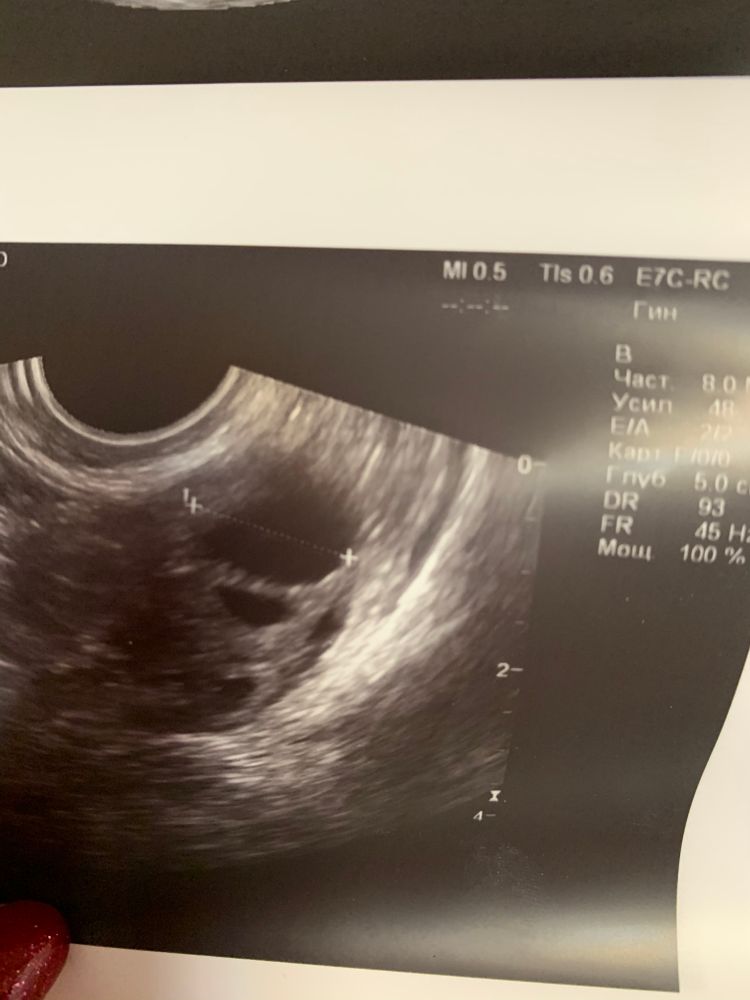

Дальше иду в другую клинику на 16 дц, там уверенно мне говорят есть киста жт с кровотоком ( даже показала) и жидкость овуляция была день -два назад . Вот фото

Сегодня 19 дц пошла к третьему специалисту , она говорит нет это дф перерос в кисту. Не было овуляции . Но у неё аппарат я так понимаю без кровотока..